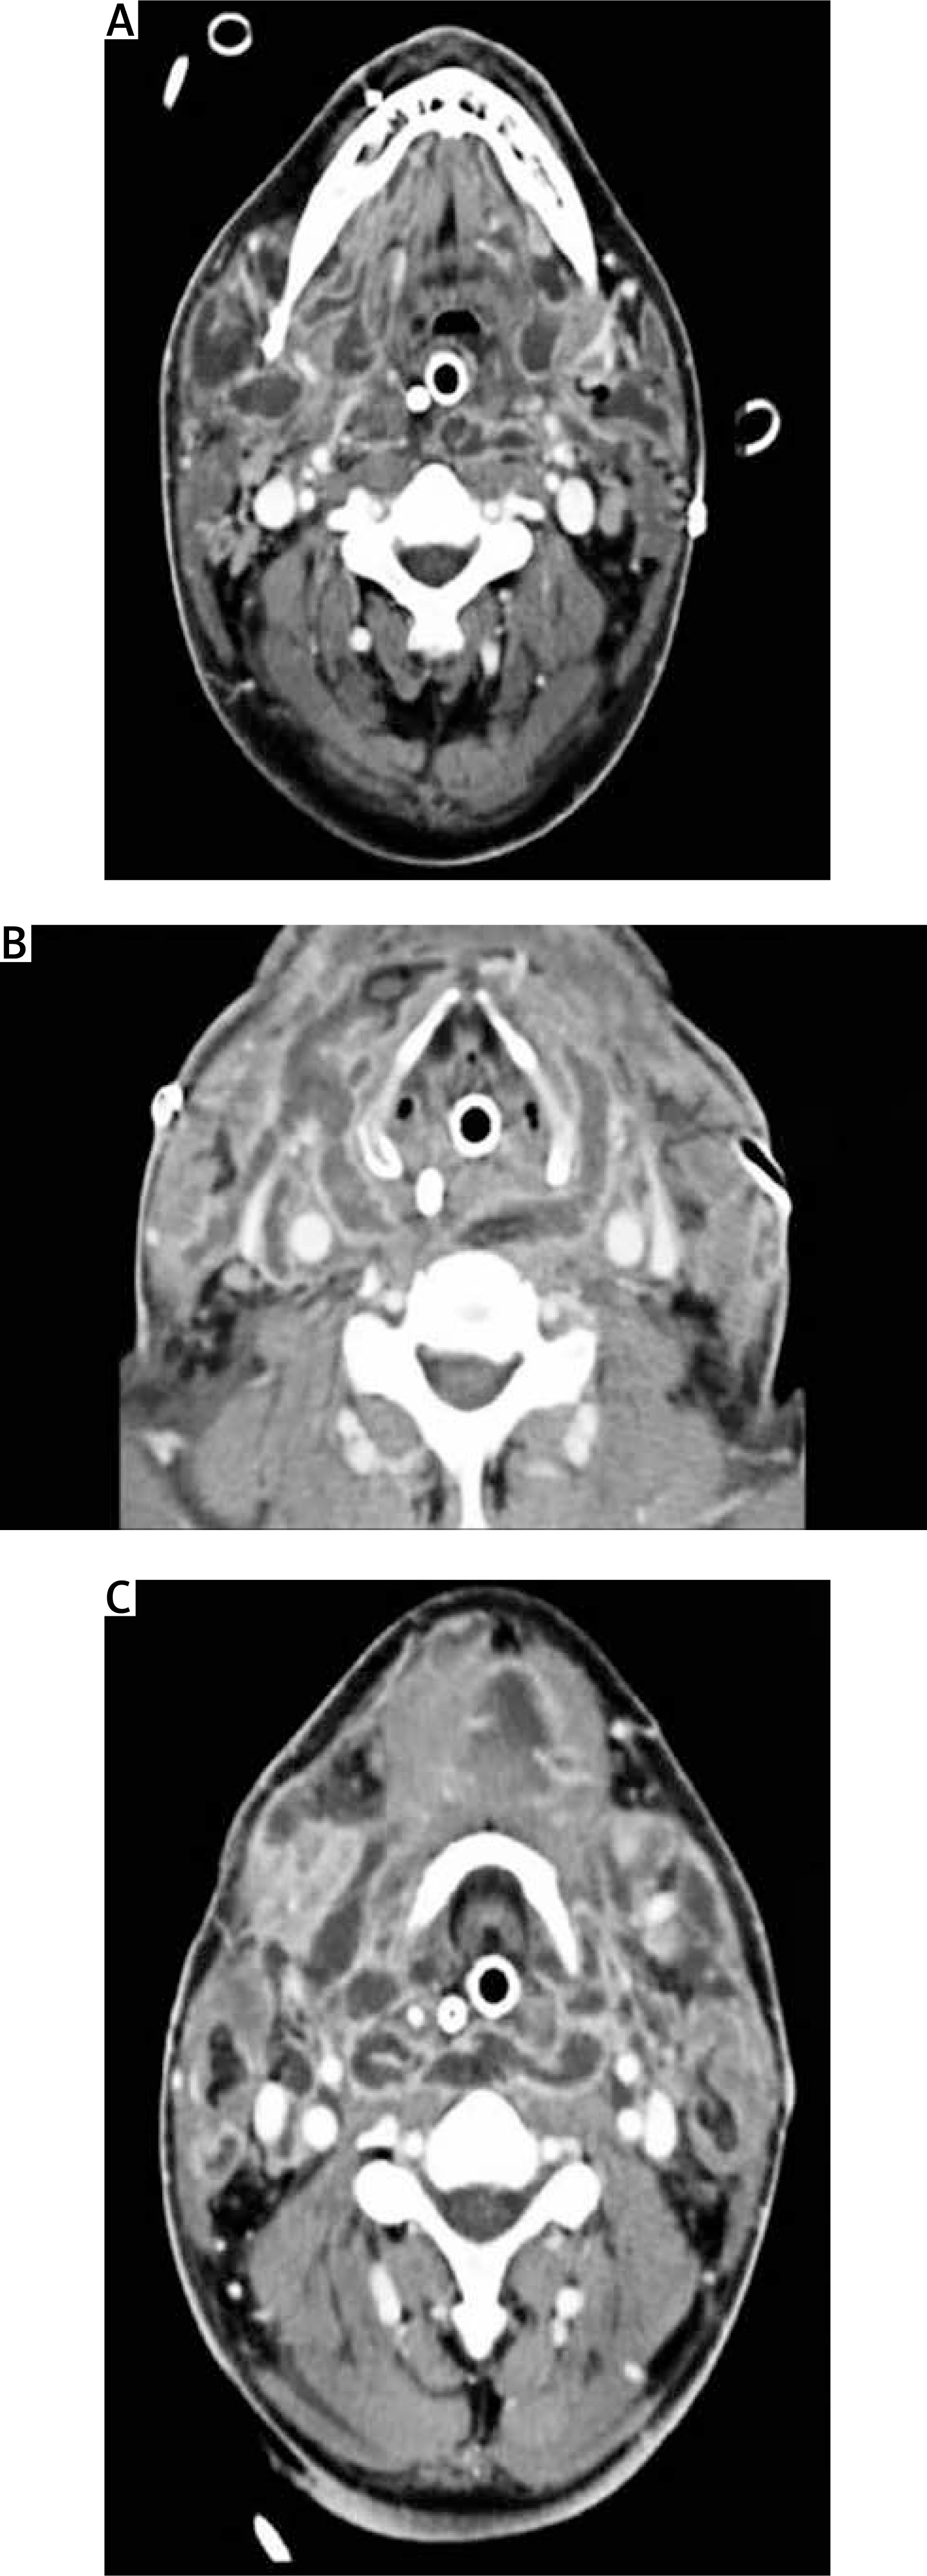

Clinical signs and initial infectious site are summarized in Table I. All our patients benefited from a preoperative chest and neck CT allowing us to specify the site and the extent of the infection (Figures 1–4). We adopt diagnostic criteria of DNM defined by Estrera and colleagues including: clinical manifestation of severe oropharyngeal infection (odontogenic, peritonsillar, or retropharyngeal abscesses, Ludwig’s angina, or infection secondary to traumatic pharyngeal perforations), demonstration of characteristic roentgenographic features of DNM, documentation of mediastinitis during the operation or postmortem examination, or both; and establishment of the relation between oropharyngeal infection and development of DNM.

Figure 1

A–C – Transversal views of a rhino cervical scan with multiple beginning infectious collections